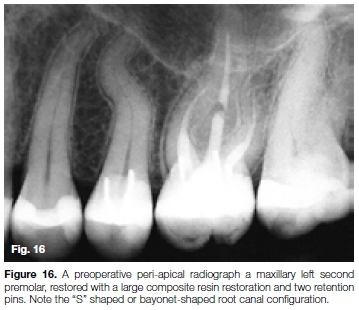

The patient, a 37 year old female presented with irreversible pulpitis on her maxillary left first second premolar. The tooth had been previously restored with a large composite resin restoration and two retention pins. A preoperative peri-apical radiograph (Figure 16) and a length determination radiograph (Figure 17) revealed and confirmed a challenging "S" shaped or bayonet-shaped root canal configuration.